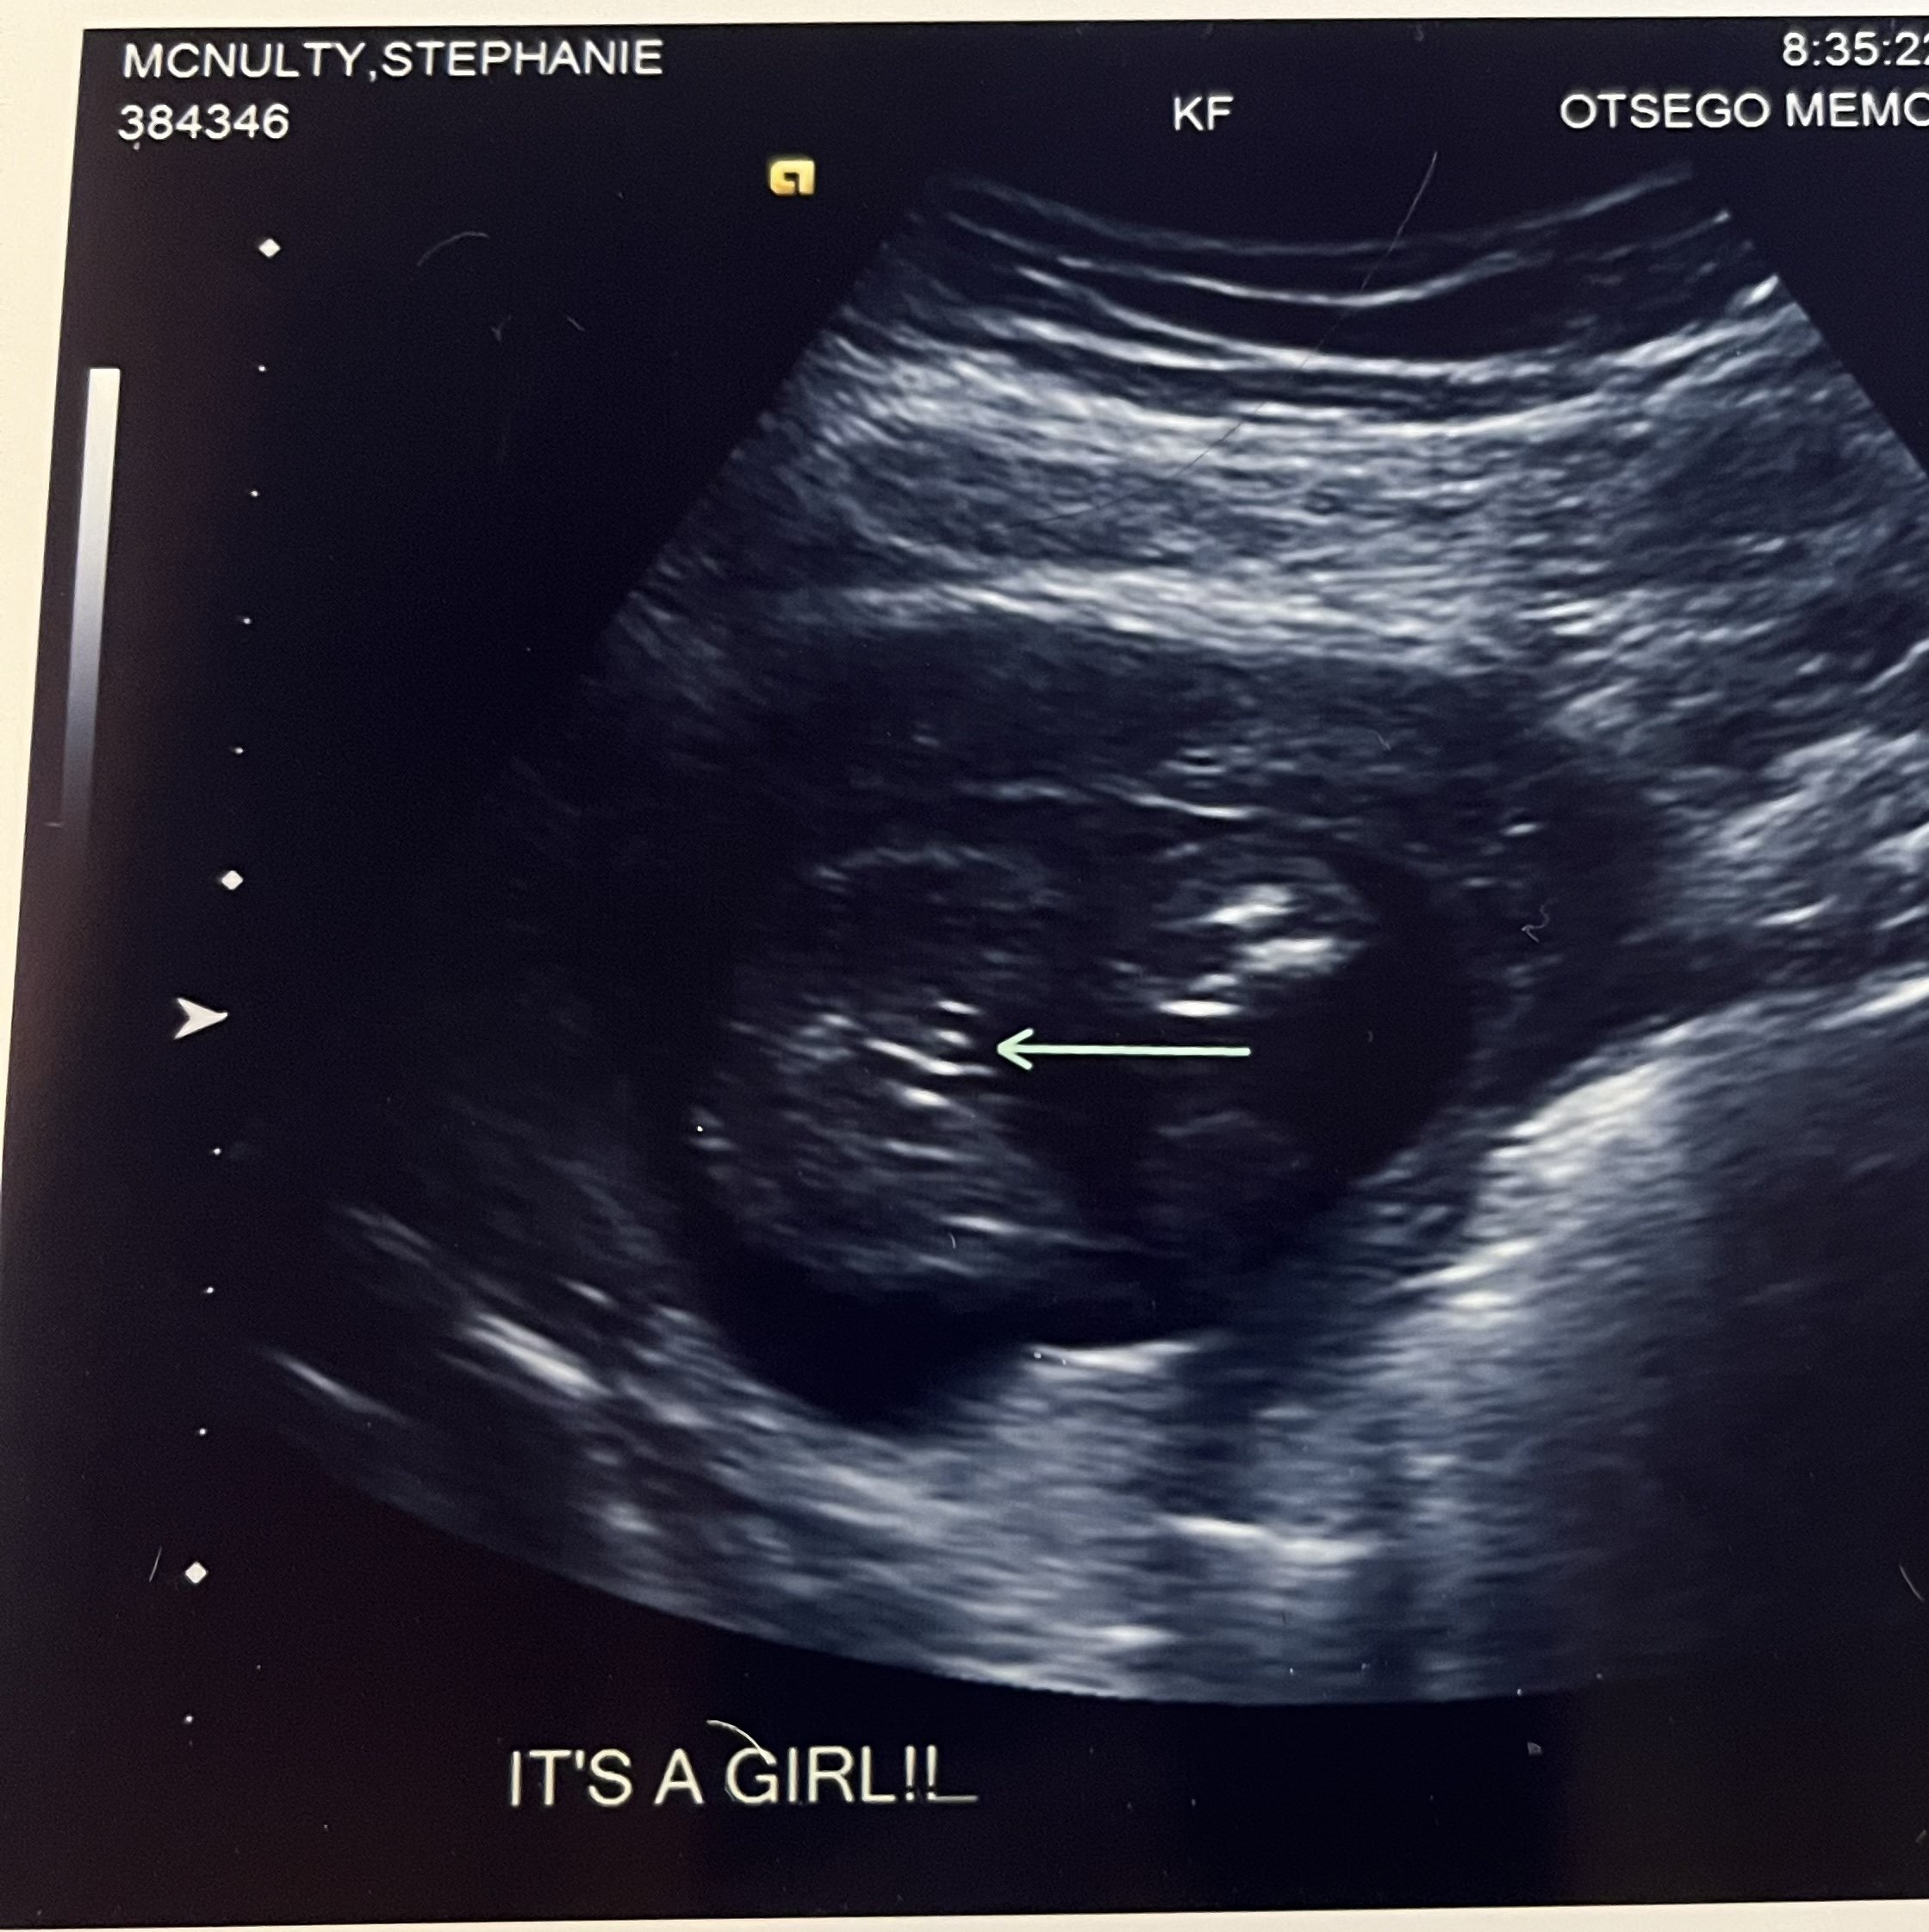

Holy cow guys! It’s a girl! Just found out today. We are STUNNED! I think we both just had it in our heads that it was a boy and it is not and that’s weird but - baby looks healthy and well!!!